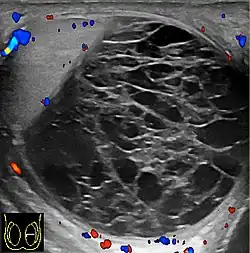

Patients with testicular lymphoma are usually old aged around 60 years of age, present with painless testicular enlargement and less commonly with other systemic symptoms such as weight loss, anorexia, fever and weakness. Bilateral testicle involvements are common and occur in 8.5% to 18% of cases. At sonography, most lymphomas are homogeneous and diffusely replace the testis [Fig. 7]. However focal hypoechoic lesions can occur, hemorrhage and necrosis are rare. At times, the sonographic appearance of lymphoma is indistinguishable from that of the germ cell tumors [Fig. 8], then the patient's age at presentation, symptoms, and medical history, as well as multiplicity and bilaterality of the lesions, are all important factors in making the appropriate diagnosis.

Primary leukemia of the testis is rare. However, due to the presence of blood-testis barrier, chemotherapeutic agents are unable to reach the testis, hence in boys with acute lymphoblastic leukemia, testicular involvement is reported in 5% to 10% of patients, with the majority found during clinical remission. The sonographic appearance of leukemia of the testis can be quite varied, as the tumors may be unilateral or bilateral, diffuse or focal, hypoechoic or hyperechoic. These findings are usually indistinguishable from that of the lymphoma [Fig. 9].

-

Fig. 9. Leukemia. Diffuse hypoechoic infiltrative lesions are seen involving the whole testis, indistinguishable from that of the lymphoma.